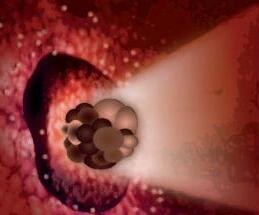

La pagina a fianco mostra l'immagine di una cellula tumorale reale, visualizzata al microscopio elettronico, che ingrandisce questa cellula 6500 volte rispetto alle sue normali dimensioni. Questo tipo di cellula prende il nome di carcinoma, cioè derivante da cellule epiteliali, il tipo di cellule che rivestono sia le superfici interne (polmoni, intestini) che esterne (pelle) del corpo.

Grazie a questo ingrandimento si possono identificare chiaramente alcune delle caratteristiche di tutte le cellule tumorali: a) l'enorme nucleo cellulare dalla forma insolita che spiega la loro grande capacità di riprodursi e b) la struttura non uniforme, complessa della superficie cellulare, che riflette una forte attività di secrezione di sostanze prodotte dalle cellule tumorali.

Una delle più importanti molecole secrete dalle cellule tumorali in grandi quantità sono gli enzimi a ‘forbice’ che digeriscono il collagene. Sono aggiunti graficamente a questa immagine, sotto forma di strutture simili ad un ‘pacman’ rosso.

La foto nella pagina a fianco mostra una cellula cancerogena ad un microscopio.

Il corpo di questa cellula tumorale in migrazione si espande nella direzione del suo movimento all’interno del tessuto. Può formare una struttura ‘tentacolare’ che trascina la cellula tumorale lungo la superficie, in questo caso, di un vaso sanguigno.

Gli enzimi che digeriscono il collagene sono aggiunti per illustrare il processo mediante il quale qualsiasi ostacolo sul cammino di questa cellula tumorale viene superato.